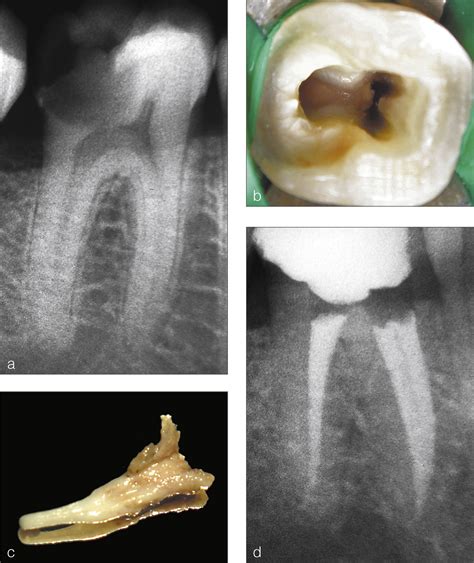

La anatomía radicular y la configuración de los conductos de los primeros molares inferiores representan un reto importante, incluso para el endodoncista más experimentado. El tratamiento exitoso de estos molares requiere un conocimiento considerable de la curvatura de los conductos y de las variaciones anatómicas.

Además, su forma irregular, las comunicaciones interconductos y las curvaturas no son visibles en las radiografías, lo que aumenta aún más la dificultad del tratamiento. Se acepta que no existe una técnica única para la limpieza y conformación de todos los casos. Por lo tanto, los endodoncistas deben comprender completamente la morfología dentaria y la configuración de los conductos para seleccionar la modalidad de tratamiento más adecuada para cada caso.

Para poder observar con claridad la tercera raíz son necesarias varias radiografías. La obtención de una sola radiografía puede conducir con facilidad a errores de diagnóstico. La colocación de una lima en la raíz adicional puede ofrecer el aspecto de una perforación. Cuando los hallazgos radiográficos no son definitivos, la información que aportan los localizadores de ápice electrónicos nos permite hacer un diagnóstico diferencial y confirmar la presencia de conductos adicionales.

La localización del orificio requiere realizar modificaciones en las aperturas de acceso convencionales del primer molar inferior. Lo que está indicado es la extensión de la cavidad de acceso hacia el conducto distolingual para conseguir así un acceso en línea recta. El tercio coronal del conducto presenta una aguda curvatura que debe tenerse en consideración para evitar perforaciones o desgastes (stripping) y evitar la eliminación de excesivas cantidades de dentina en la cara lingual del acceso radicular del conducto accesorio.

Para conseguir resultados satisfactorios en los tratamientos de endodoncia son esenciales un buen diagnóstico y acceso, y un adecuado tratamiento del tercer conducto radicular dentro de complejo sistema. En el caso de procedimientos quirúrgicos endodóncicos, la tercera raíz representa un reto importante.